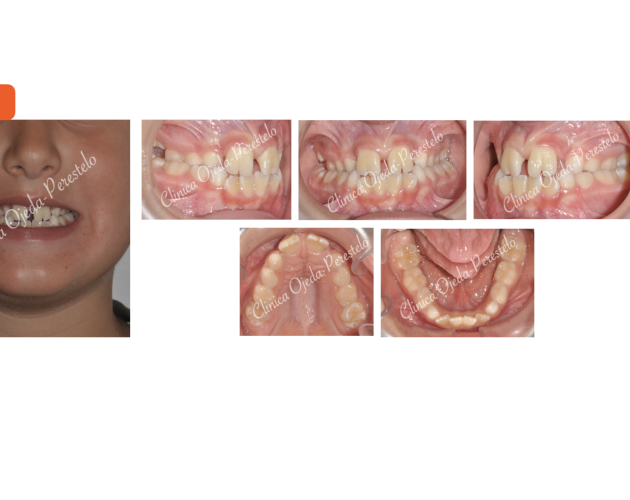

Mordida Cruzada Bilateral Casos de Éxito - Mordida Cruzada - Niños

Clase III esquelética en dentición mixta Casos de Éxito - Niños

Clase III esquelética en dentición temporal Casos de Éxito - Niños